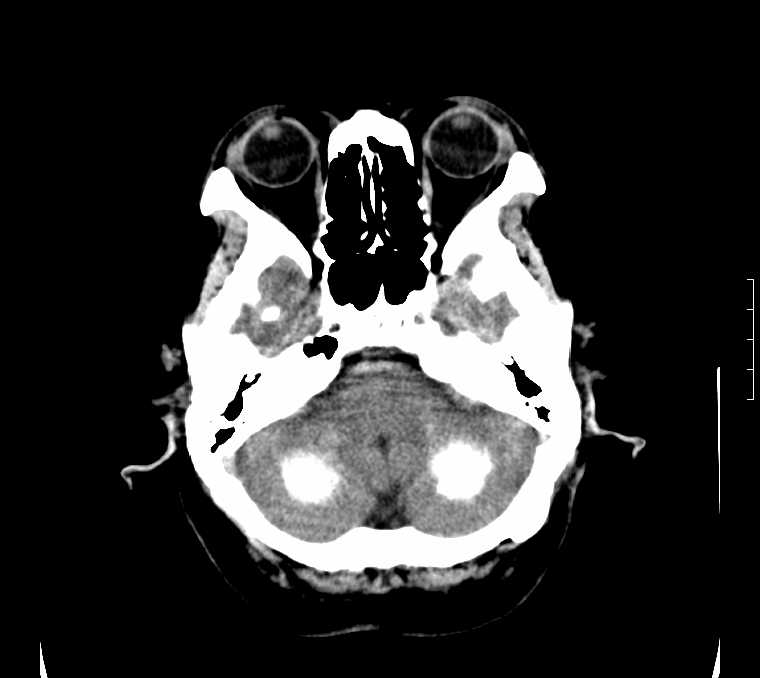

标题: CT24387:看看这例脑部改变!!

老年女性。头晕。

fahr病

鉴别于特发性家族性脑血管亚铁钙沉着症(fahr`s病)与甲状旁腺机能低下之间,请结合临床及相关实验室检查。